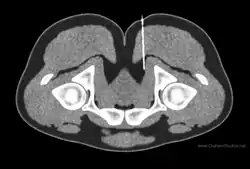

Diagnostic nerve blocks

Diagnostic nerve blocks are very effective for identifying sensory entrapment points. Their strength is that they can directly measure whether a given nerve is contributing pain, or not. They are precise and reproducible.[36] As successful blocks require accurate targeting of the nerve, this is done under image guidance such as fluoroscopy, ultrasound,[37] CT,[37] or MRI.[38] Ultrasound is popular choice because of its soft-tissue contrast, portability, lack of radiation, and low cost, but is not good at depicting deeper structures like the deep pelvic nerves. For deeper structures, CT and MRI are more appropriate, although the equipment is more expensive.[39][40][41][37][38]

The challenge with diagnostic blocks is that there is often not good information to indicate exactly where the entrapment point may be. For example, symptoms may be poorly localized,[42] and the symptoms may be imprecise.[43] Consequently, multiple blocks may need to be performed on different nerves to find the correct one. A successful diagnostic block will lead to immediate and significant resolution of symptoms up to complete pain relief.[43][44] The duration of the block will last several hours depending on the anesthetic used.[45]